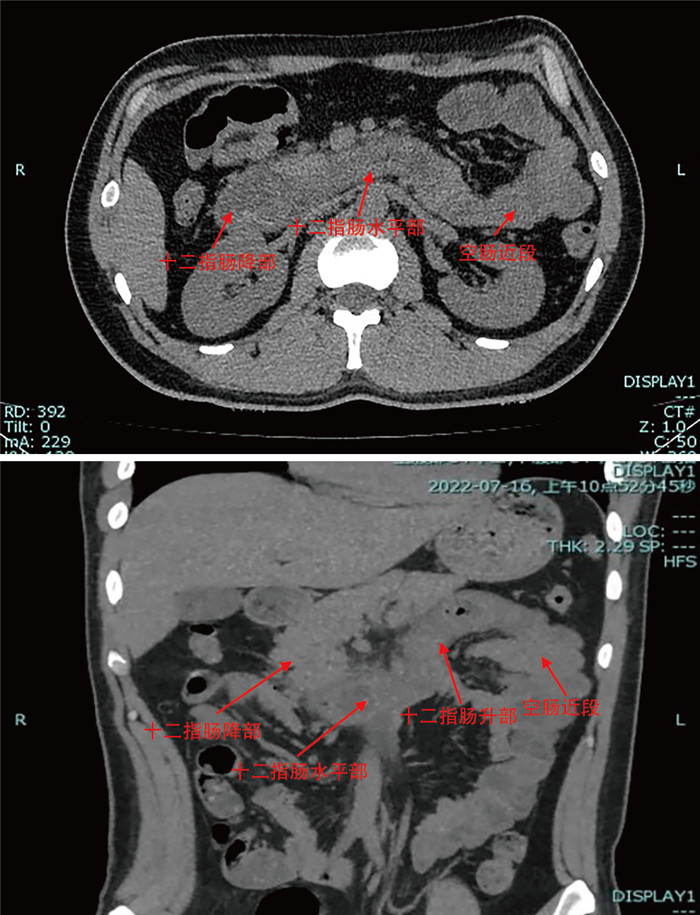

成人腹型过敏性紫癜误诊1例并文献复习

罗利绵, 李琪, 谢淼

2025, 23(7): 1262-1266. doi: 10.16766/j.cnki.issn.1674-4152.004111

443 8

摘要:

通过回顾成人腹型过敏性紫癜误诊病例,分析原因并结合临床文献资料,总结腹型过敏性紫癜疾病特点,降低误诊率。本文回顾分析了2022年7月收治的1例被误诊为急性胃肠炎的成人腹型过敏性紫癜患者的临床资料,该例患者在腹痛后期出现皮肤紫癜,同时寻求多学科会诊,更改诊断为腹型过敏性紫癜,予以糖皮质激素、抗过敏药物等对症治疗后病情好转出院。腹型过敏性紫癜少见,而成人发病率更低,因缺乏特征性临床表现及特异性辅助检查,误诊率高,临床工作者应吸取经验教训,避免误诊错治。